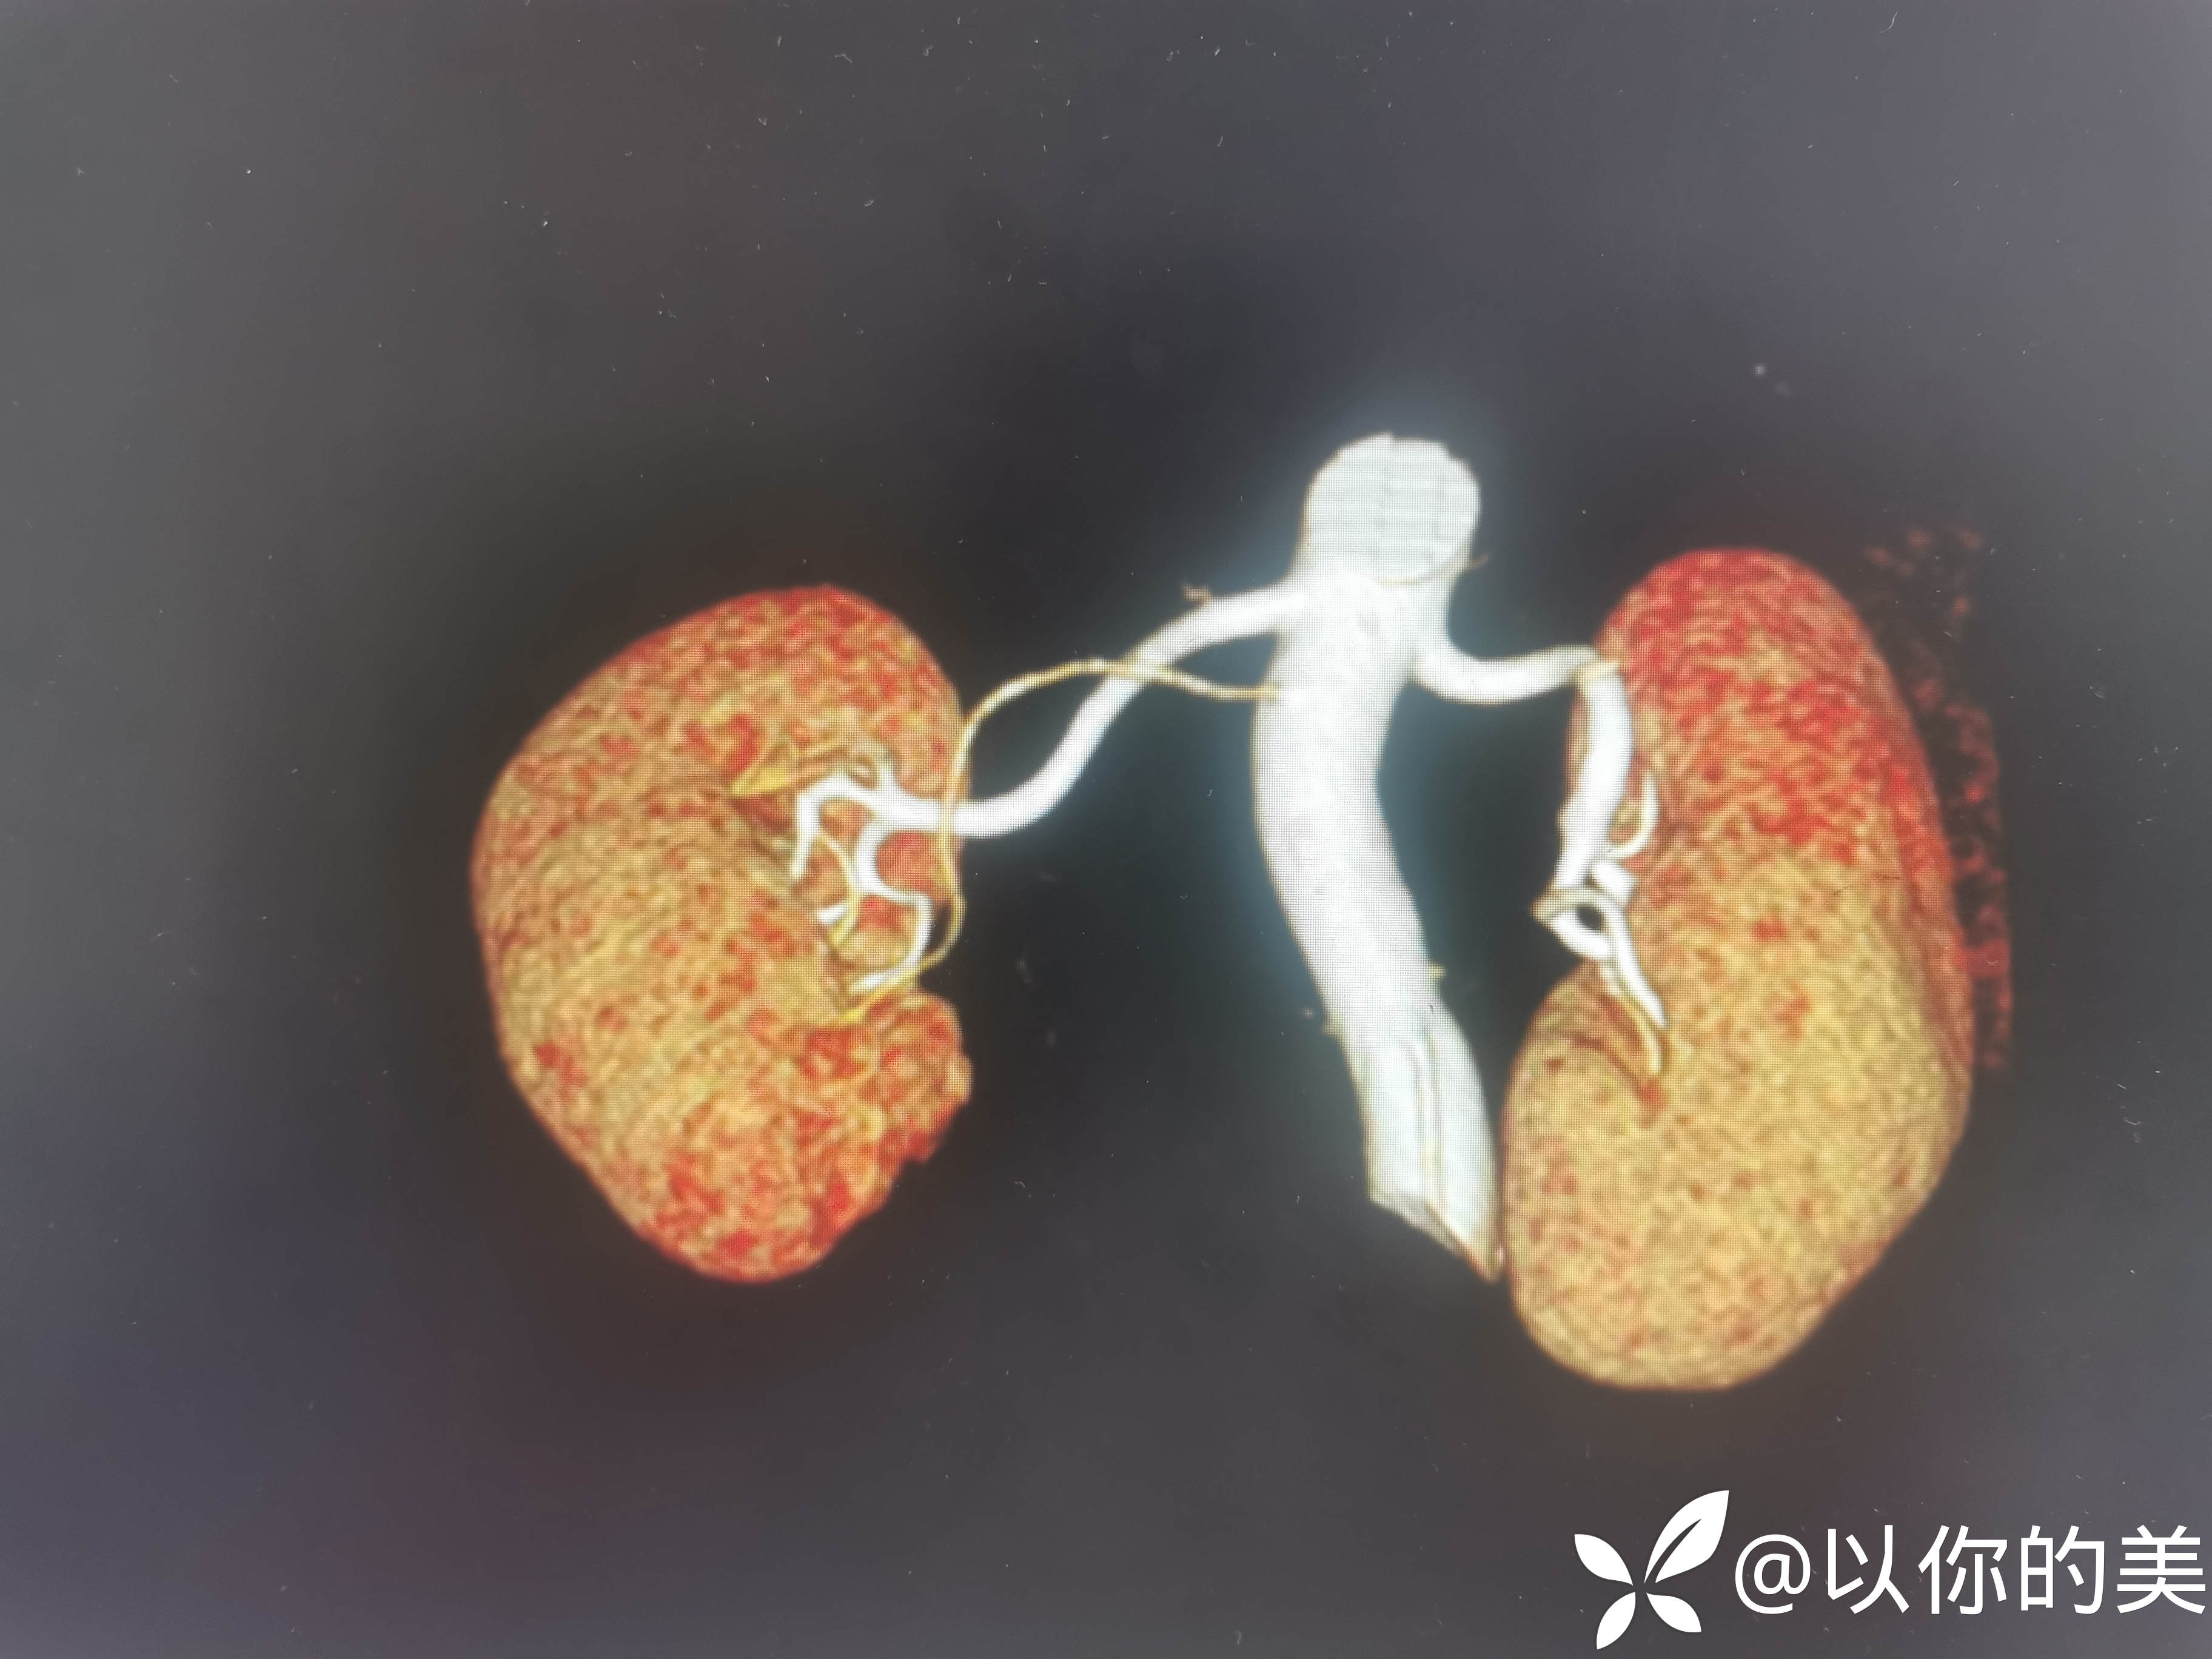

肾血管CTA:

肾血管CTA有无异常,行肾血管CTA意义何在?